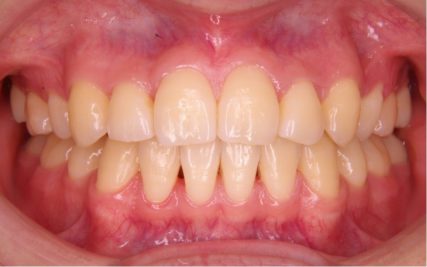

- 治療前

- 上下とも前歯のスペース不足が認められた。歯のサイズと顎の幅とのバランスが不調和な事が原因の1つとして考えられる。

- 治療後

- 前歯部のでこぼこが解消され、正常咬合を獲得する事が出来た。又、歯科矯正用アンカースクリューを用いる事で抜歯スペースを有効に利用できた。